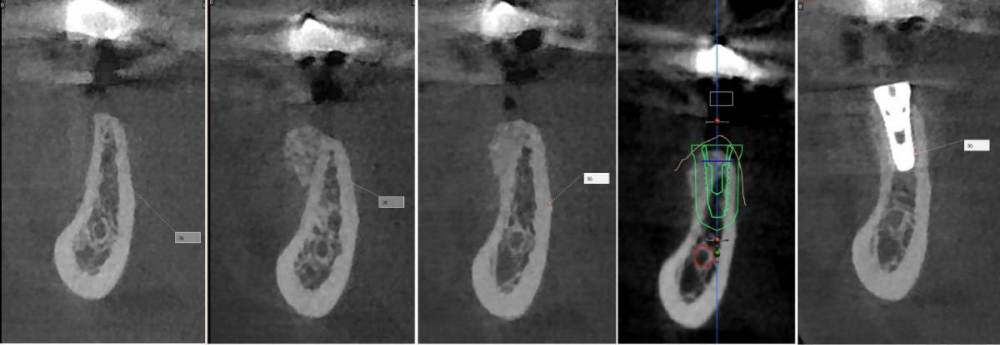

kramer Опубликовано 26 июня, 2023 Поделиться Опубликовано 26 июня, 2023 Первые три снимка в каждом ряду это до, сразу после, через 3 месяца? Ссылка на комментарий

karasov Опубликовано 26 июня, 2023 Автор Поделиться Опубликовано 26 июня, 2023 8 минут назад, Женька сказал: что за магия вне Хогвартса и как это держится?) у ТЛ осстем набор и имплантоводы подходят под хирургический шаблон?? Или мукотом и вслепую без шаблона? Вертикальный разрез кпереди от дефекта, отслаивание слизисто-надкостничного лоскута тупо кзади от разреза, введение в него шприцом графта, два шва. Графт введен вслепую с избытком-позже он лизировался,что видно на кт. SS устанавливаю стандартным набором oneguide, докручиваю имплантоводом от SS. 1 час назад, kramer сказал: Первые три снимка в каждом ряду это до, сразу после, через 3 месяца? До,сразу после, через 3 месяца, планирование, контроль Ссылка на комментарий